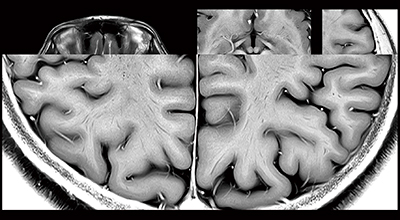

図1 32chヘッドコイルを用いた高解像度画像

2D FSE T2WI Reverse,1024マトリックス。灰白質の層構造もわかるほどの高い分解能を実現している。